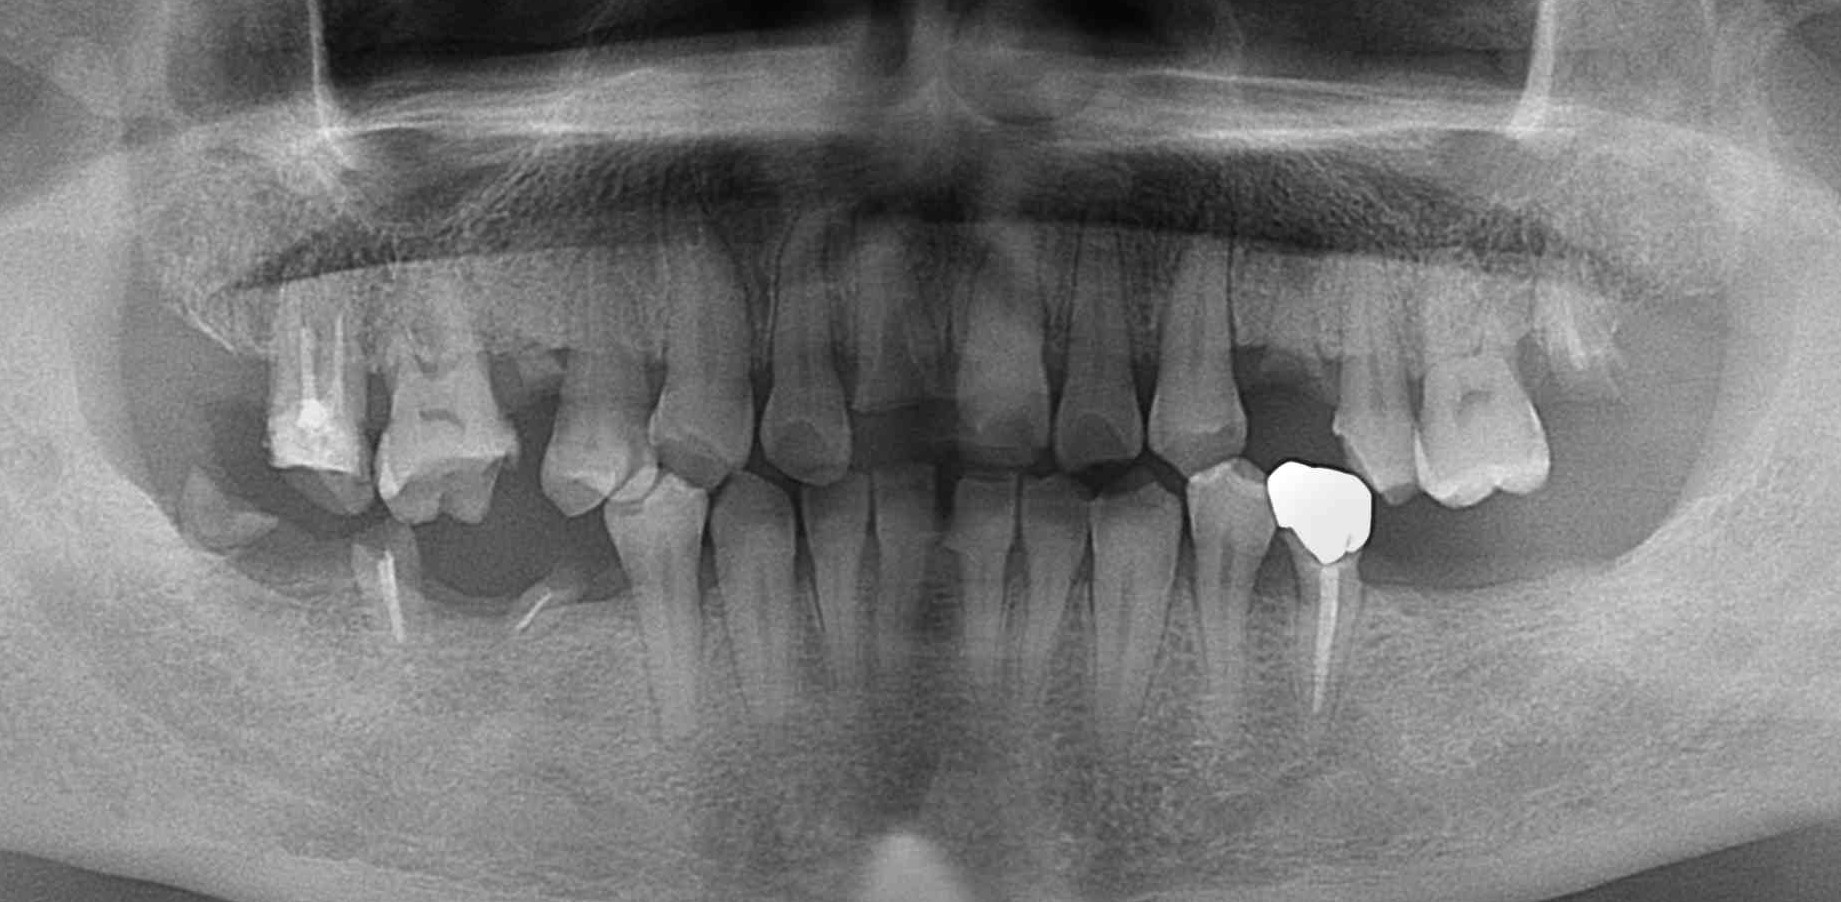

| 主訴 | 右上4番目がぐらつく 押さえると痛む |

|---|---|

| 年齢・性別 | 57歳 男性 |

| 治療期間・回数 | 8か月 10回 |

| 費用 | CT 15,000 骨造成 85,000 インプラント 270,000 |

| 備考 | CT画像より右上4番の近心歯周ポケットが根尖近くまで存在し、口蓋側まで繋がっており、予後不良と判断してインプラント治療を行う予定とした。 右上5番は口蓋側に根尖付近のポケットがあったが咬合性外傷による動揺であり、保存可能と判断。 4番骨造成時にフラップ手術を行った。 |